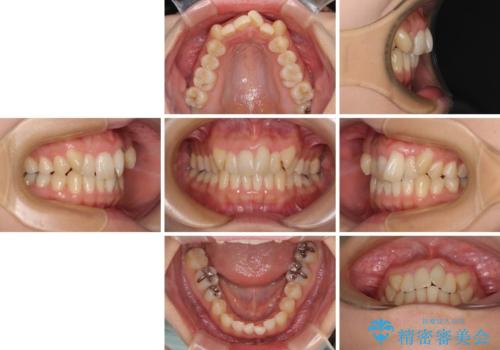

- 目立つ八重歯を気にして来院された患者様です。

下顎歯列の叢生は軽度であることと、口元の突出感が全くなかったことから、八重歯解消のために上顎左右第一小臼歯を抜歯し、ワイヤー装置にて矯正治療を行うこととしました。

八重歯をスムーズに解消するために、補助装置を用いることで速やかに歯列を整えることができました。